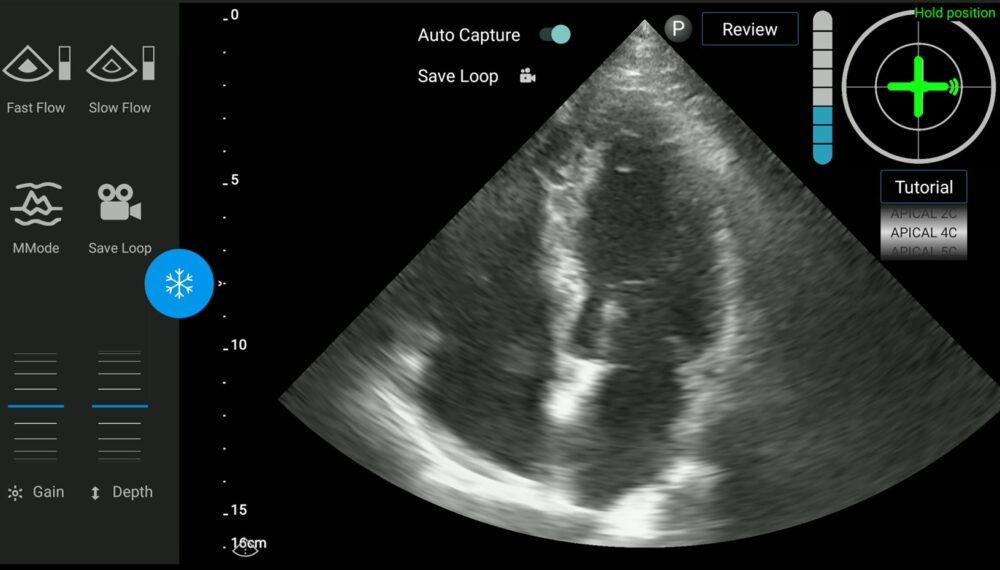

Over Zoom, Vortman demonstrated for ISRAEL21c how UltraSight works. On screen is a blue cross and a gray cross. The latter represents the heart. The operator simply guides the blue cross until it is over the gray cross. When the blue cross turns green, the ultrasound device is ready to snap a picture.

“Simplifying the cardiac image acquisition process makes this scalable,” Vortman tells ISRAEL21c. “You don’t have to be a cardiologist or a sonographer. The operator can be a nurse or a paramedic.”

Vortman notes that some 20 percent of cardiac ultrasound images “are of suboptimal quality, meaning they cannot be used for decision making. If we can improve that, it will represent a major change in the industry.”

The interpretation of that image is a separate process; UltraSight’s software makes it easy to share the picture with an off-site expert.